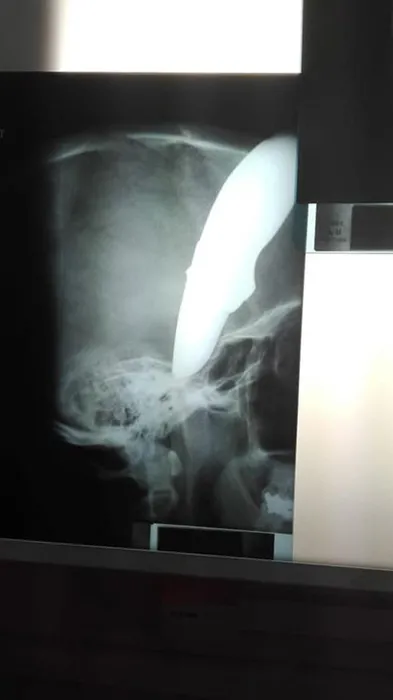

Başına saplanmış 15 cm'lik bıçakla kurtuldu!

Hastaneye sakince yürüyerek geldi ve "Müsait bir doktor var mı?" diye sordu.

Ancak 34 yaşındaki Shaun Wayne'i görenler küçük dilini yuttu. Wayne'in kafatasına saplanmış 15 santimetrelik bir  vardı.

Güney Afrika'da sahil kenti Cape Town yakınlarında iki adamın saldırısına uğrayan bisikletçi Wayne, başından kanlar damlayarak hastaneye ulaşmayı başardı.

Hemen ameliyata alınan ve mucizevi bir şekilde hayatta kalan adamın fotoğrafı ise, sosyal medyada viral oldu. Bisikletçinin annesine kafatasının tamamen iyileşeceğini söyleyen Dr. Brendan Venter, Wayne'nin çok şanslı olduğunu belirtti.

Yerel medya, 34 yaşındaki erkeğin bisikletini gasp etmek isteyen saldırganların  kullandığını bildiriyor.